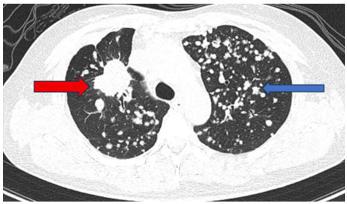

- Chụp cắt lớp vi tính lồng ngực:

Hình 3: Hình ảnh sau các đợt điều trị:  Các tổn thương của phổi (giảm số lượng và kích thước sau các đợt điều trị).

Hình 4: Hình ảnh sau các đợt điều trị:  Các tổn thương của xương (không thay đổi số lượng và kích thước sau các đợt điều trị).

Như vậy, bệnh nhân đáp ứng khá tốt với Gefitinib: chất chỉ điểm khối u, kích thước tổn thương phổi có xu hướng giảm dần.